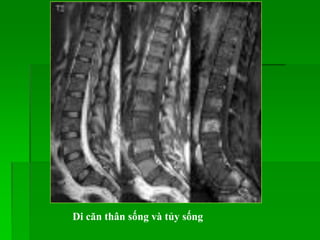

Lymphoma

- Thường gặp ở 40-60 tuổi, nam >nữ.

- MRI: tín hiệu thấp trên T1W, cao không đồng nhất trên T2W,

bắt Gd sau tiêm, có thể gây hủy xương hay chèn ép tủy.

Lymphoma : dày lan tỏa và bắt Gd của chùm đuôi ngựa